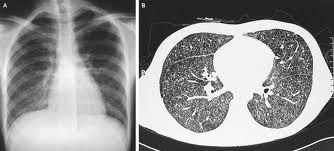

miliary-tb.jpg

• Chest x-ray showing miliary shadows.